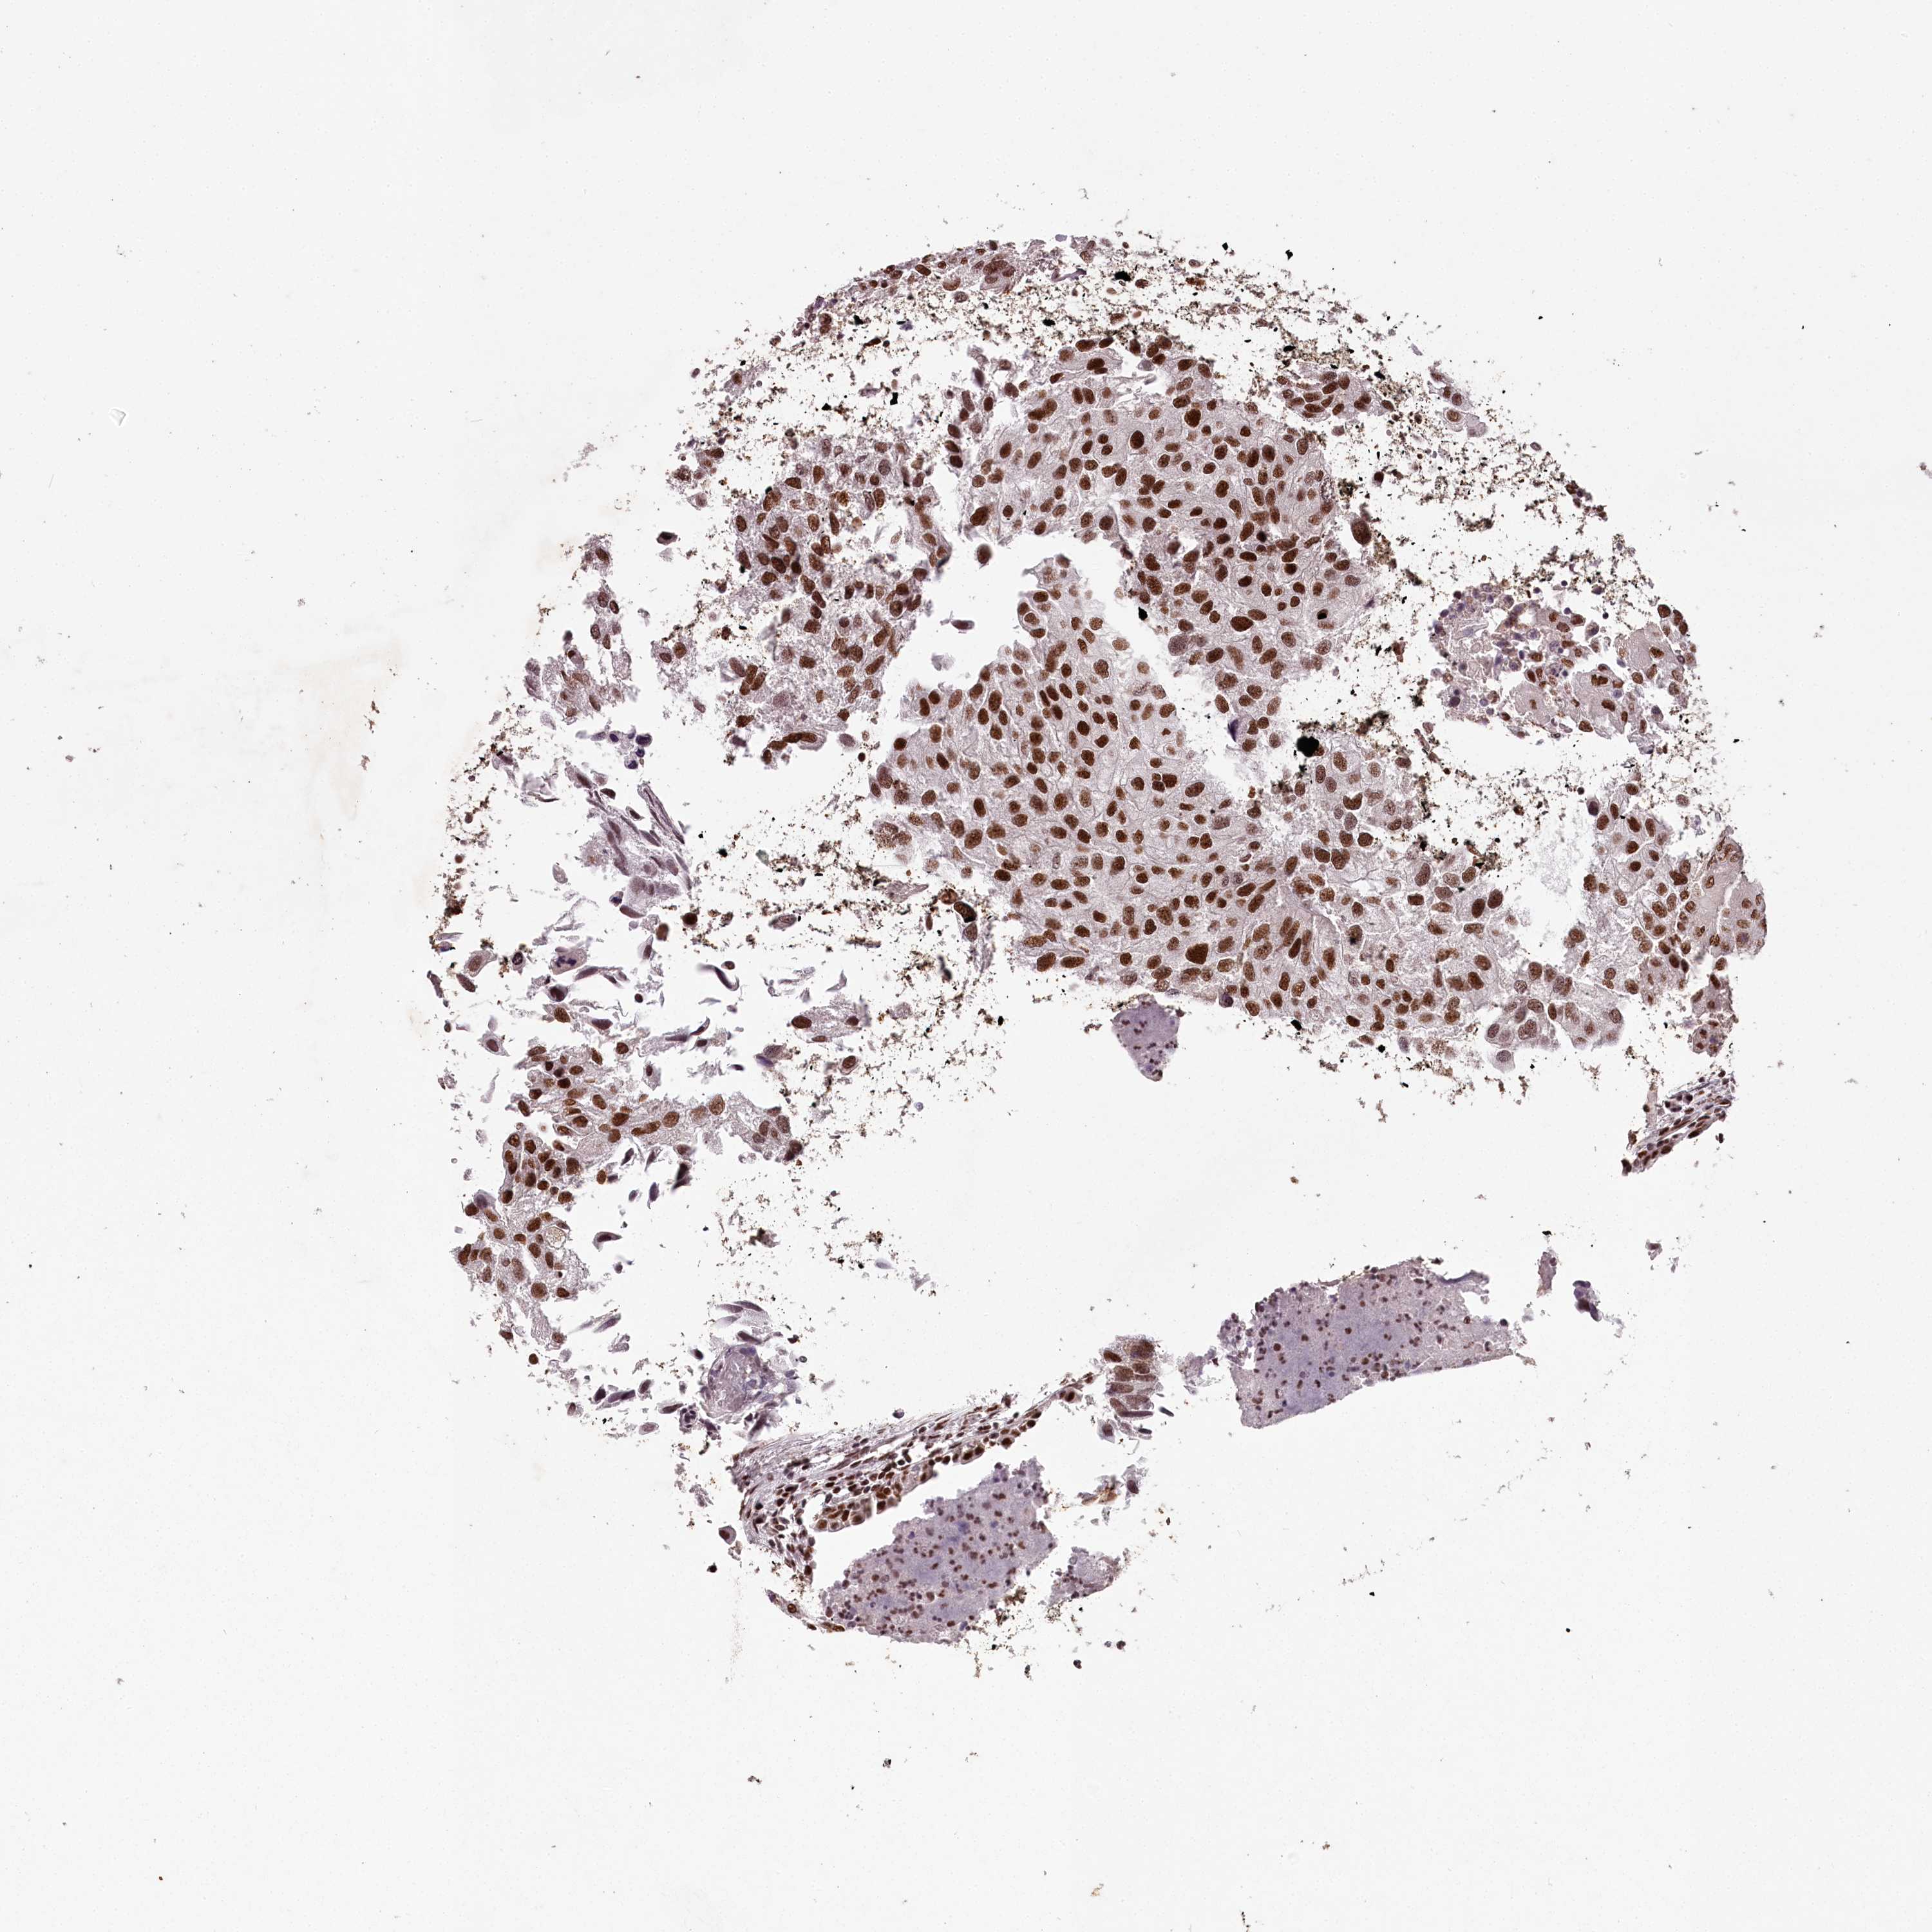

UROTHELIAL CANCER - Protein expressioni

A mouse-over function shows sample information and annotation data. Click on an image to view it in a full screen mode. Samples can be filtered based on level of antibody staining by selecting one or several of the following categories: high, medium, low and not detected. The assay and annotation is described here.

Antibody stainingi

Antibody staining in the annotated cell types in the current human tissue is reported as not detected, low, medium, or high, based on conventional immunohistochemistry profiling in selected tissues. This score is based on the combination of the staining intensity and fraction of stained cells.

Each image is clickable and will lead to virtual microscopy that enables deeper exploration of all samples and also displays staining intensity scores, fraction scores and subcellular localization as well as patient and tissue information for each sample.

Antibody HPA038904

Staining

High

Medium

Low

Not detected

Intensity

Strong

Moderate

Weak

Negative

Quantity

>75%

75%-25%

<25%

None

Location

Nuclear

Cytoplasmic/membranous

Cytoplasmic/membranous,nuclear

Urothelial carcinoma, High grade

Urothelial carcinoma, Low grade